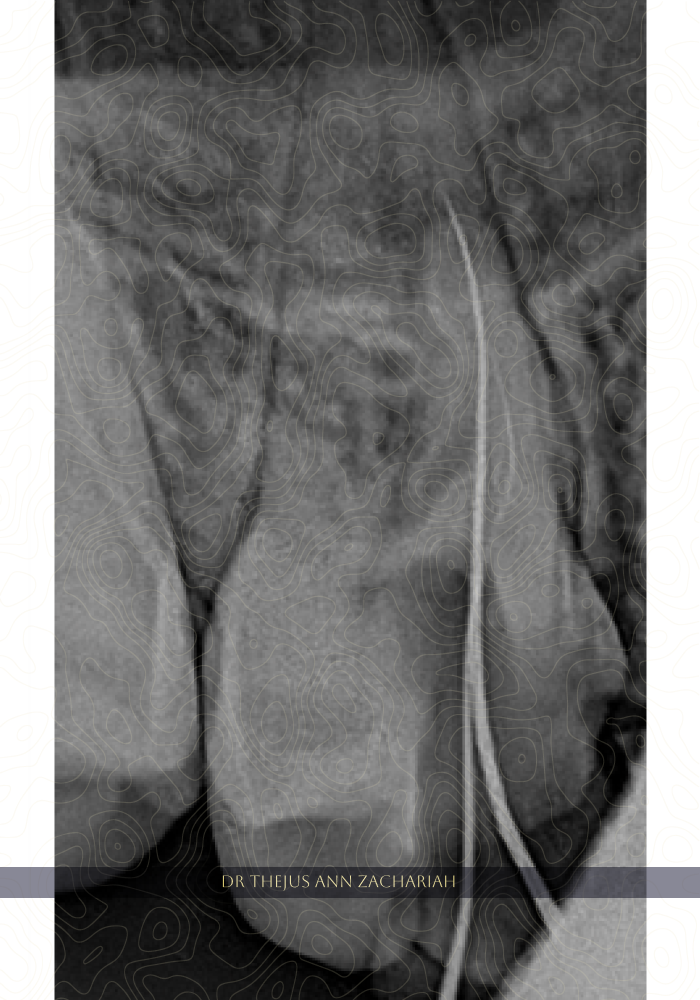

Master Cone

alt text